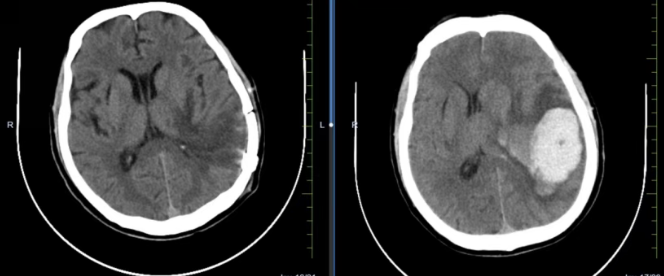

神经外科医师紧急会诊评估:患者深度昏迷,双侧瞳孔不等大,对光反射迟钝。这些是神经急危重症的典型表现。时间就是生命,医院第一时间启动急危重症应急预案,开通绿色通道。头颅CT检查迅速明确了病因:左侧颞顶叶脑出血,并已出现脑疝迹象。

手术室内,神经外科团队在神经内镜等设备辅助下,进行手术以清除血肿、降低致命的颅内高压。术后复查显示,患者脑内血肿被成功清除,受压的脑组织得到有效减压。